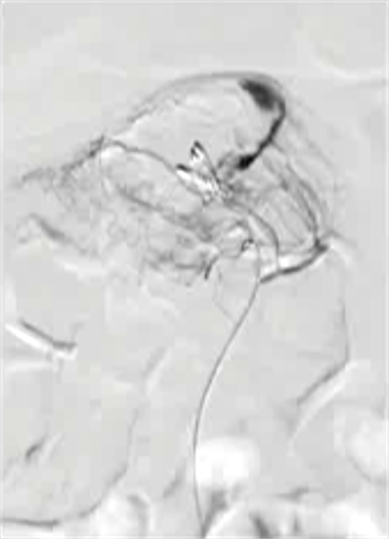

Empiric Colonic Embo Case

Bleeding into diverticulum

Region of bleeding tic

Post embo |